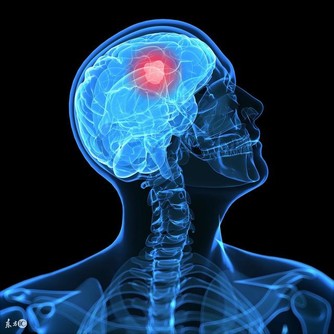

⑥定期檢查。時不時地就自己觀察身體有沒有變化,而且不管身體如何,每年都要做體檢,及時知道身體狀況。